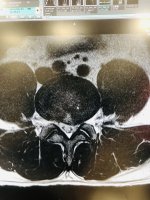

"Trọng Hoàng phát hiện mắc chứng thoát vị đĩa đệm trong đợt tập trung đội tuyển Việt Nam hồi tháng 9/2021 và phải nghỉ thi đấu tới nay. Lần gần nhất anh ra sân thi đấu trong trận tuyển Việt Nam thua Australia 0-1 ở vòng loại thứ ba World Cup 2022 hôm 3/9/2021. Hơn một năm qua, tiền vệ xứ Nghệ theo nhiều phương pháp điều trị nhưng thời gian đầu không hiệu quả. Anh sau đó quyết định phẫu thuật và tập phục hồi tại một trung tâm hồi phục chấn thương thể thao tại TP HCM do bác sĩ của đội tuyển quốc gia Trần Huy Thọ trực tiếp hướng dẫn"Mày sai rồi, Trọng Hoàng điều trị bảo tồn, nó sang Sing bên đó bảo mổ nó đéo mổ, về việt nam điều trị bảo tồn 3 thâng ok luôn.

Thông tin chính thống, mày tìm báo nào cũng ra, ko lại bảo tao bốc phét